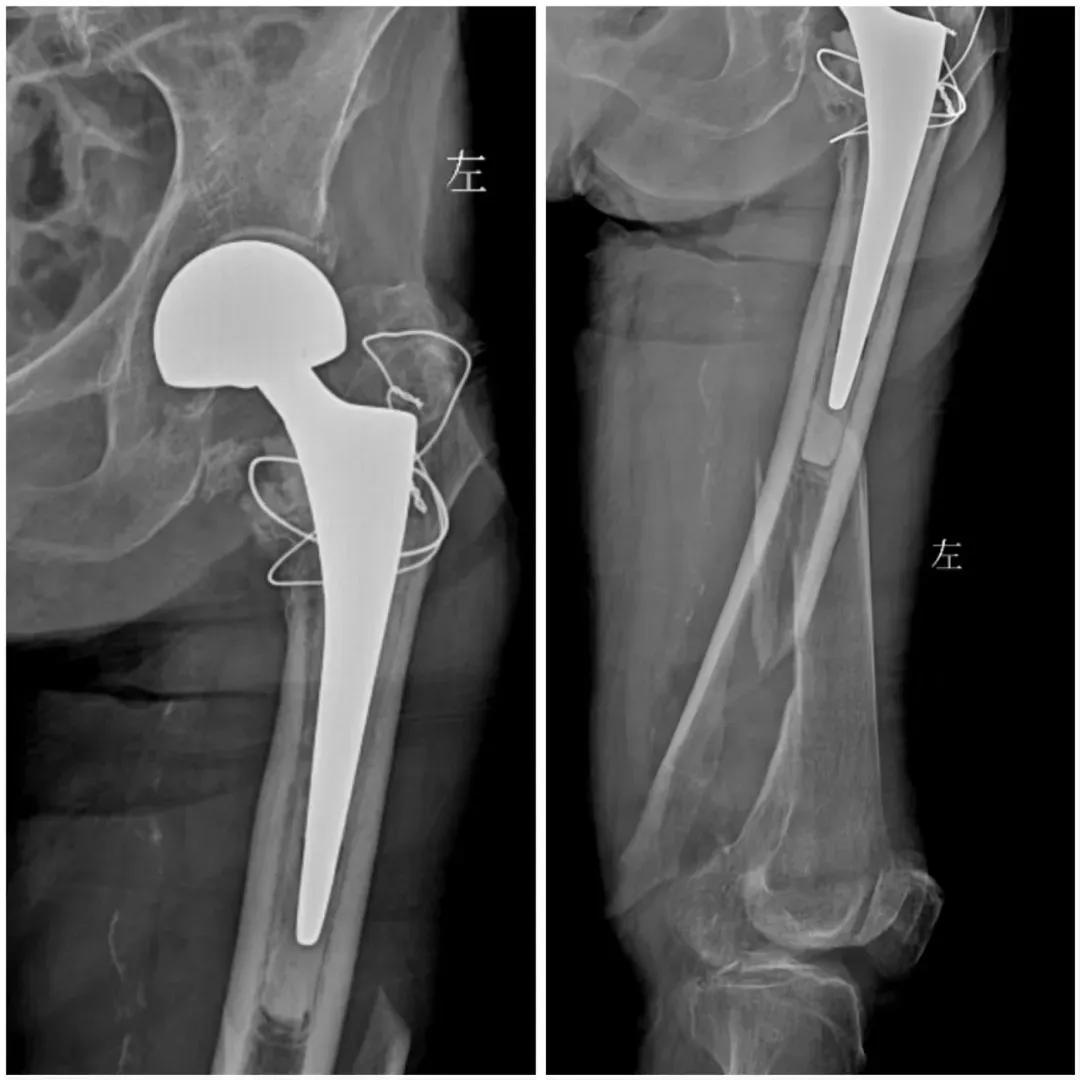

案例一

94歲的患者在家中疊被子時不慎摔倒,導(dǎo)致左下肢疼痛伴活動受限。家屬緊急將其送往渭北中心醫(yī)院。急診DR檢查顯示:左側(cè)股骨中段骨折,左側(cè)人工股骨頭置換術(shù)后改變。

術(shù)前

入院后,關(guān)節(jié)骨科(骨一科)團隊迅速對患者進行全面評估,經(jīng)過影像科、呼吸內(nèi)科、麻醉科、醫(yī)務(wù)科等多學(xué)科會診討論(MDT),考慮到患者高齡及復(fù)雜病情,決定實施左股骨干骨折切開復(fù)位內(nèi)固定術(shù)。

術(shù)后

手術(shù)由經(jīng)驗豐富的關(guān)節(jié)骨科(骨一科)曹主任主刀。術(shù)中,關(guān)節(jié)骨科(骨一科)團隊憑借精湛的技術(shù)和豐富的經(jīng)驗,精準完成骨折復(fù)位和內(nèi)固定,手術(shù)過程順利,患者生命體征平穩(wěn)。術(shù)后,患者在醫(yī)護人員的精心照料下,患者恢復(fù)良好,左下肢疼痛明顯減輕,活動能力逐步恢復(fù)?;颊呒凹覍賹κ中g(shù)效果非常滿意,對醫(yī)護人員的專業(yè)技術(shù)和服務(wù)表示衷心感謝。